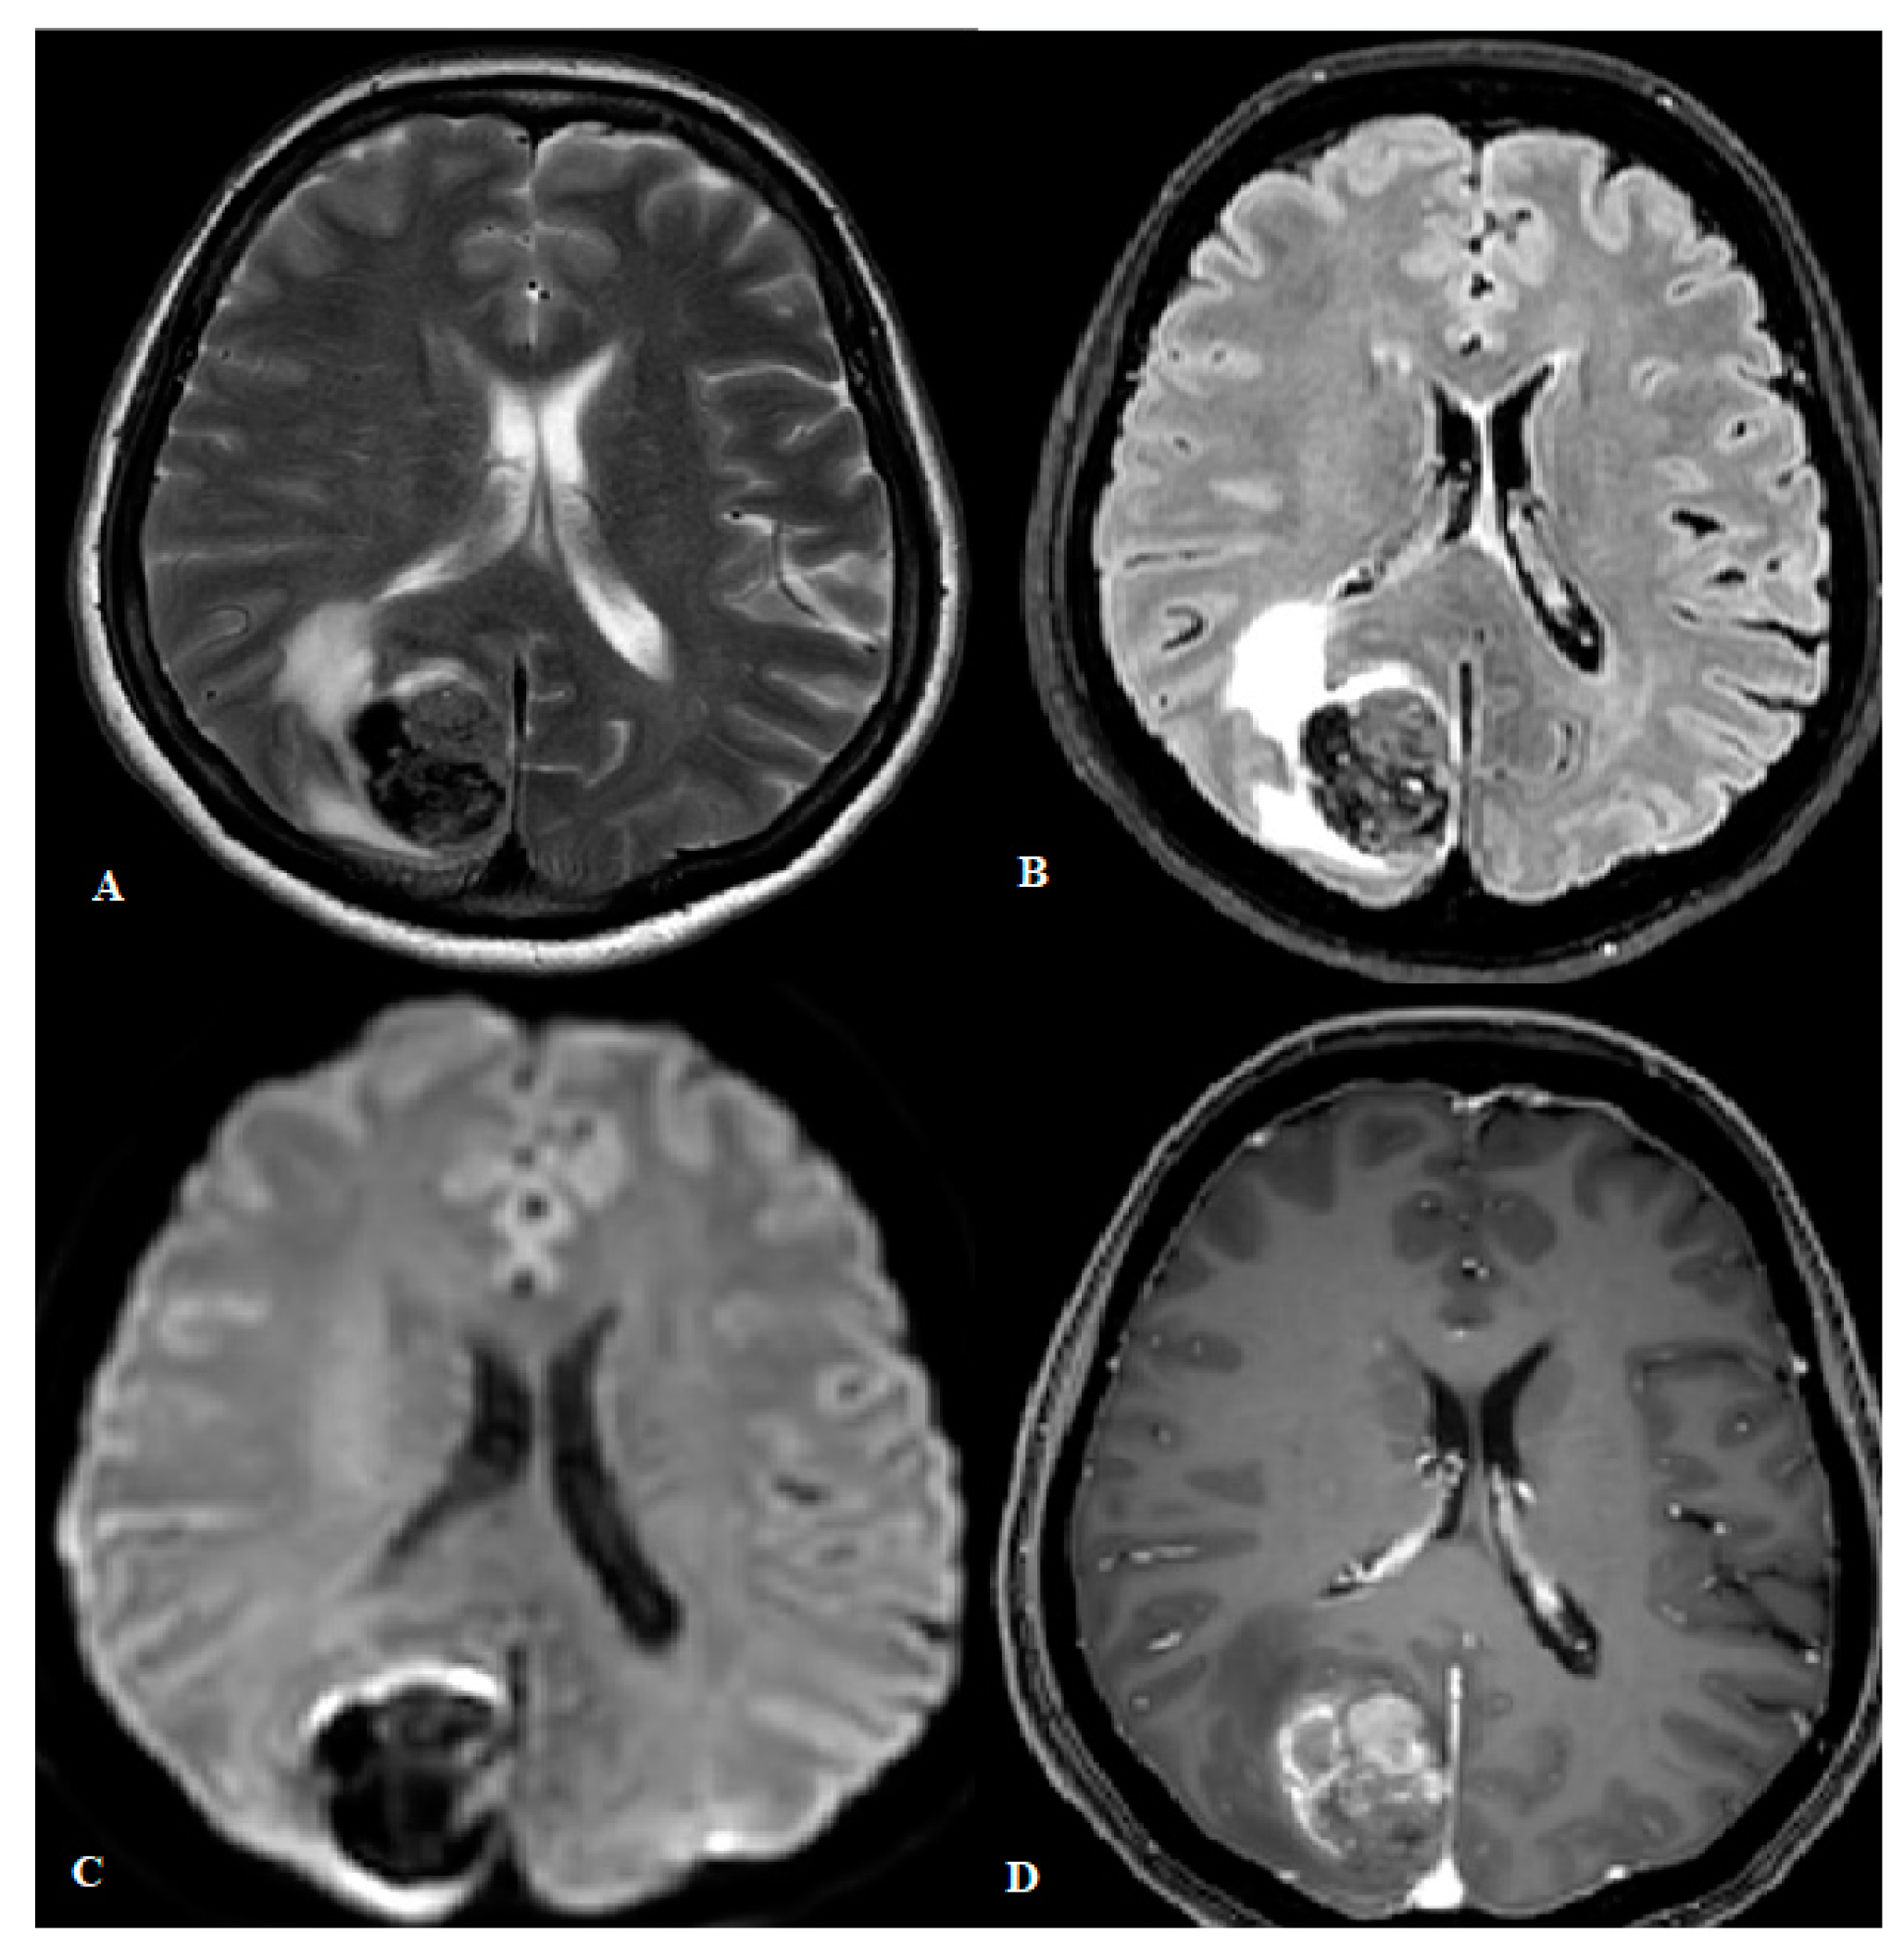

4.2. Magnetic Resonance Imaging (MRI)